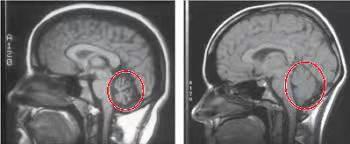

我们的小脑主要参与躯体平衡和肌肉张力的调节,因此小脑萎缩的患者可以出现步态不稳,共济失调,言语不清等症状。

虽然小脑萎缩在老年人比较多见,但是也可见于一些遗传性、变性性疾病,也可见于某些急性病程如急性小脑炎的后期及某些药物中毒等。

对于可能引起小脑萎缩的遗传性疾病,比如脊髓小脑变性(SCA)、Friedreich型共济失调、齿状核红核苍白球路易体萎缩症等。这些疾病先不赘述,想仔细了解的可以自己去搜一下。